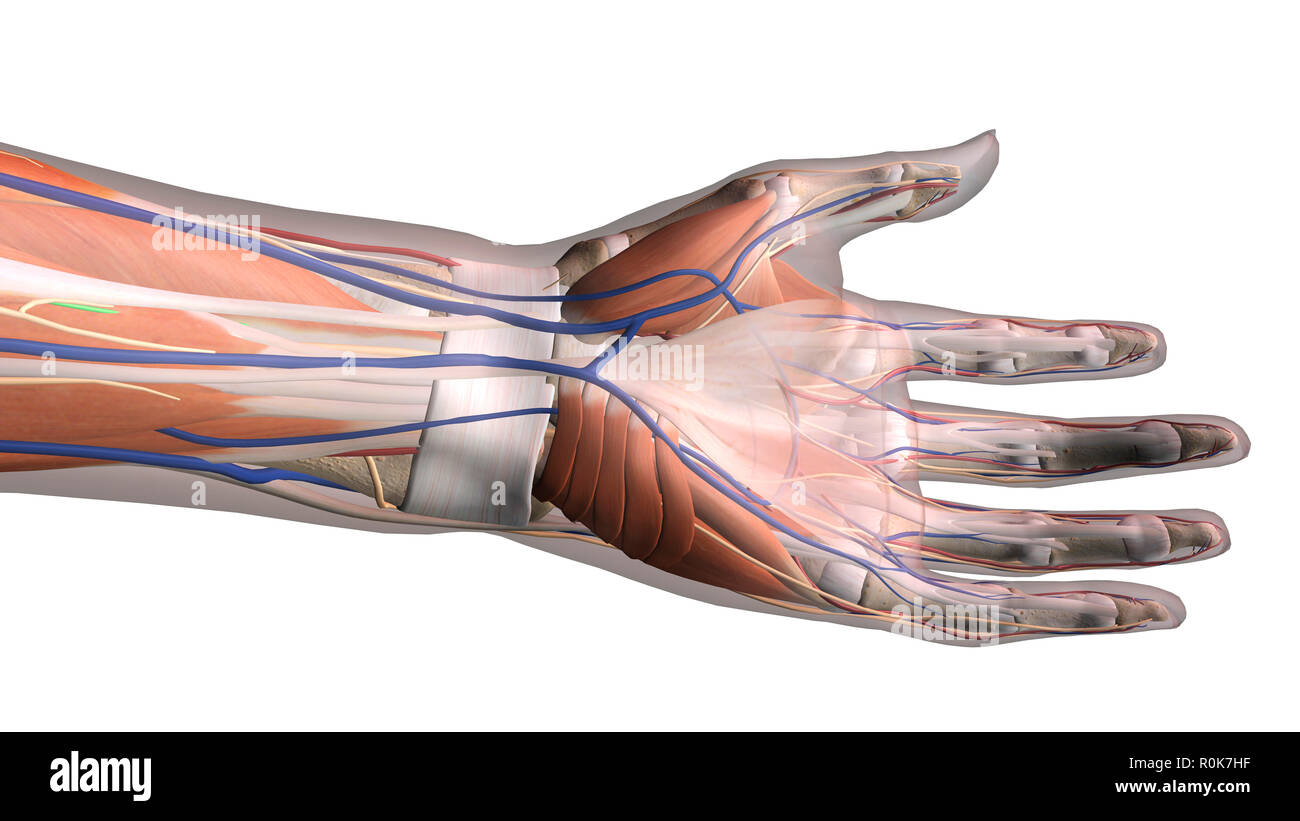

Hand anatomy, ventral view on white background. Stock Photohttps://www.alamy.com/image-license-details/?v=1https://www.alamy.com/hand-anatomy-ventral-view-on-white-background-image224157851.html

Hand anatomy, ventral view on white background. Stock Photohttps://www.alamy.com/image-license-details/?v=1https://www.alamy.com/hand-anatomy-ventral-view-on-white-background-image224157851.htmlRFR0K7HF–Hand anatomy, ventral view on white background.